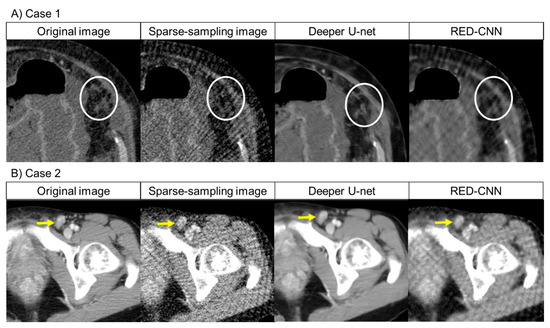

For normal local lesions and abnormal lesions, representative images of the original CT and denoised CT obtained using deeper U-net and RED-CNN are shown in Figure 2. Additionally, representative images of the original CT, the sparse-sampled CT images before denoised processing and denoised CT obtained using deeper U-net and RED-CNN are shown in Figure 3.

Figure 3.

Representative images of the original CT, sparse-sampling CT before denoising, and denoised CT obtained using deeper U-net and RED-CNN. Note: (A) Case 1: Visual scores of peritoneal dissemination (white circle): 4 points for deeper U-net, 1 points for RED-CNN for reader 1; 4 points for deeper U-net, 1 points for RED-CNN for reader 2. (B) Case 2: Visual scores of lymph node metastasis (yellow arrow): 5 points for deeper U-net, 2 points for RED-CNN for reader 1; 4 points for deeper U-net, 2 points for RED-CNN for reader 2. (C) Case 3: Visual scores of liver metastasis (red arrow): 4 points for deeper U-net, 2 points for RED-CNN for reader 1; 4 points for deeper U-net, 2 points for RED-CNN for reader 2. (D) Case 4: Visual scores of peritoneal dissemination (red arrow): 4 points for deeper U-net, 2 points for RED-CNN for reader 1; 4 points for deeper U-net, 1 points for RED-CNN for reader 2.